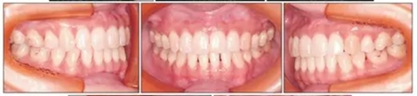

治療后面部和口內(nèi)照片顯示治療結(jié)果很成功(Figure 8)?;颊叩拿嫘瞳@得了非常顯著的改善,尤其是在唇部區(qū)域。覆合從-3.5mm增大到3.5mm,覆蓋從1.2mm增大到2.0mm。獲得了I類磨牙關(guān)系,沒有擁擠(Figures8 and 9)。

保持2年后,患者的面型和咬合關(guān)系獲得了良好的維持,并且患者對治療結(jié)果非常滿意(Table 1, Figure 12)。任一側(cè)都沒有出現(xiàn)顳下頜關(guān)節(jié)紊亂情況。